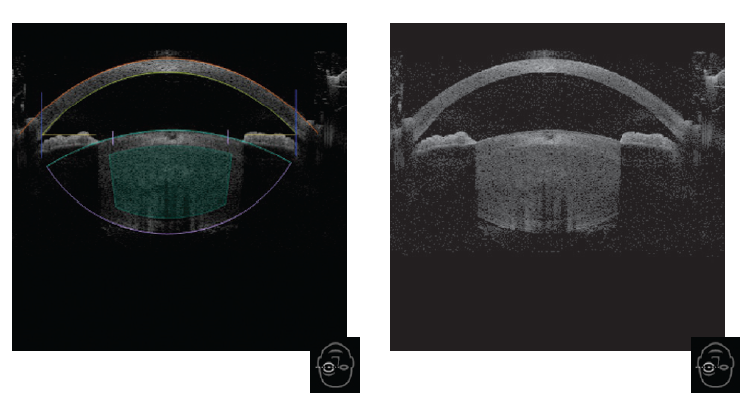

Cavitation vacuoles, which were obtained as a result of PP by YAG laser, did not interfere with the high quality visualization of the anterior segment structures by the optical coherence tomography (OCT) system of the FSL and the accuracy of planned femtosecond action (Fig. 3).

Fig. 3. Optical coherence tomography of the anterior segment of the eye